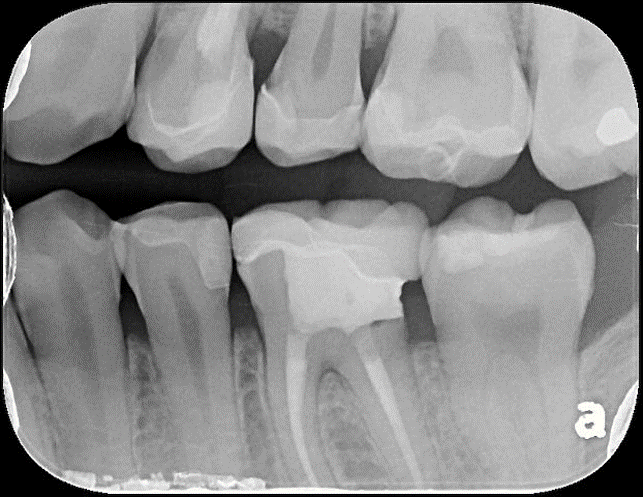

根尖片顯示邊緣密接良好